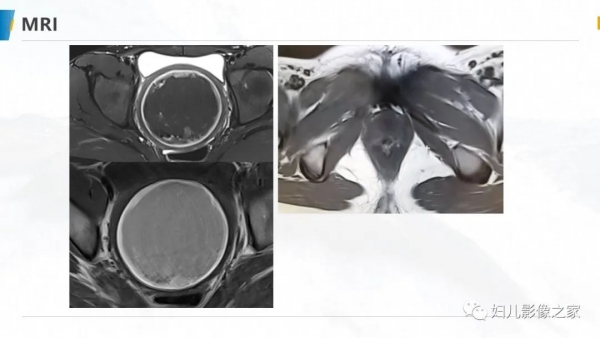

病例1

女,10岁,以“间断下腹痛7天”为主诉入院。入院查体:生命体征平稳, 心肺听诊无异常,腹软,肝脾未及,余无明显异常。

专科检查:外阴发育尚可,处女膜开口较小,棉签探入约4cm,无膨 隆,肛诊:子宫、宫颈膨隆,最低处距处女膜约4cm。

辅助检查:彩超(县中医院,2021-10-08):子宫体积增大,子 宫肌层变薄,内膜线消失,宫腔扩张,子宫颈管扩张,内充满大量液 性暗区,呈密集点状,阴道未见明显扩张。提示:1.胆囊内强回声2.胆 囊壁毛糙3.考虑处女膜闭锁。